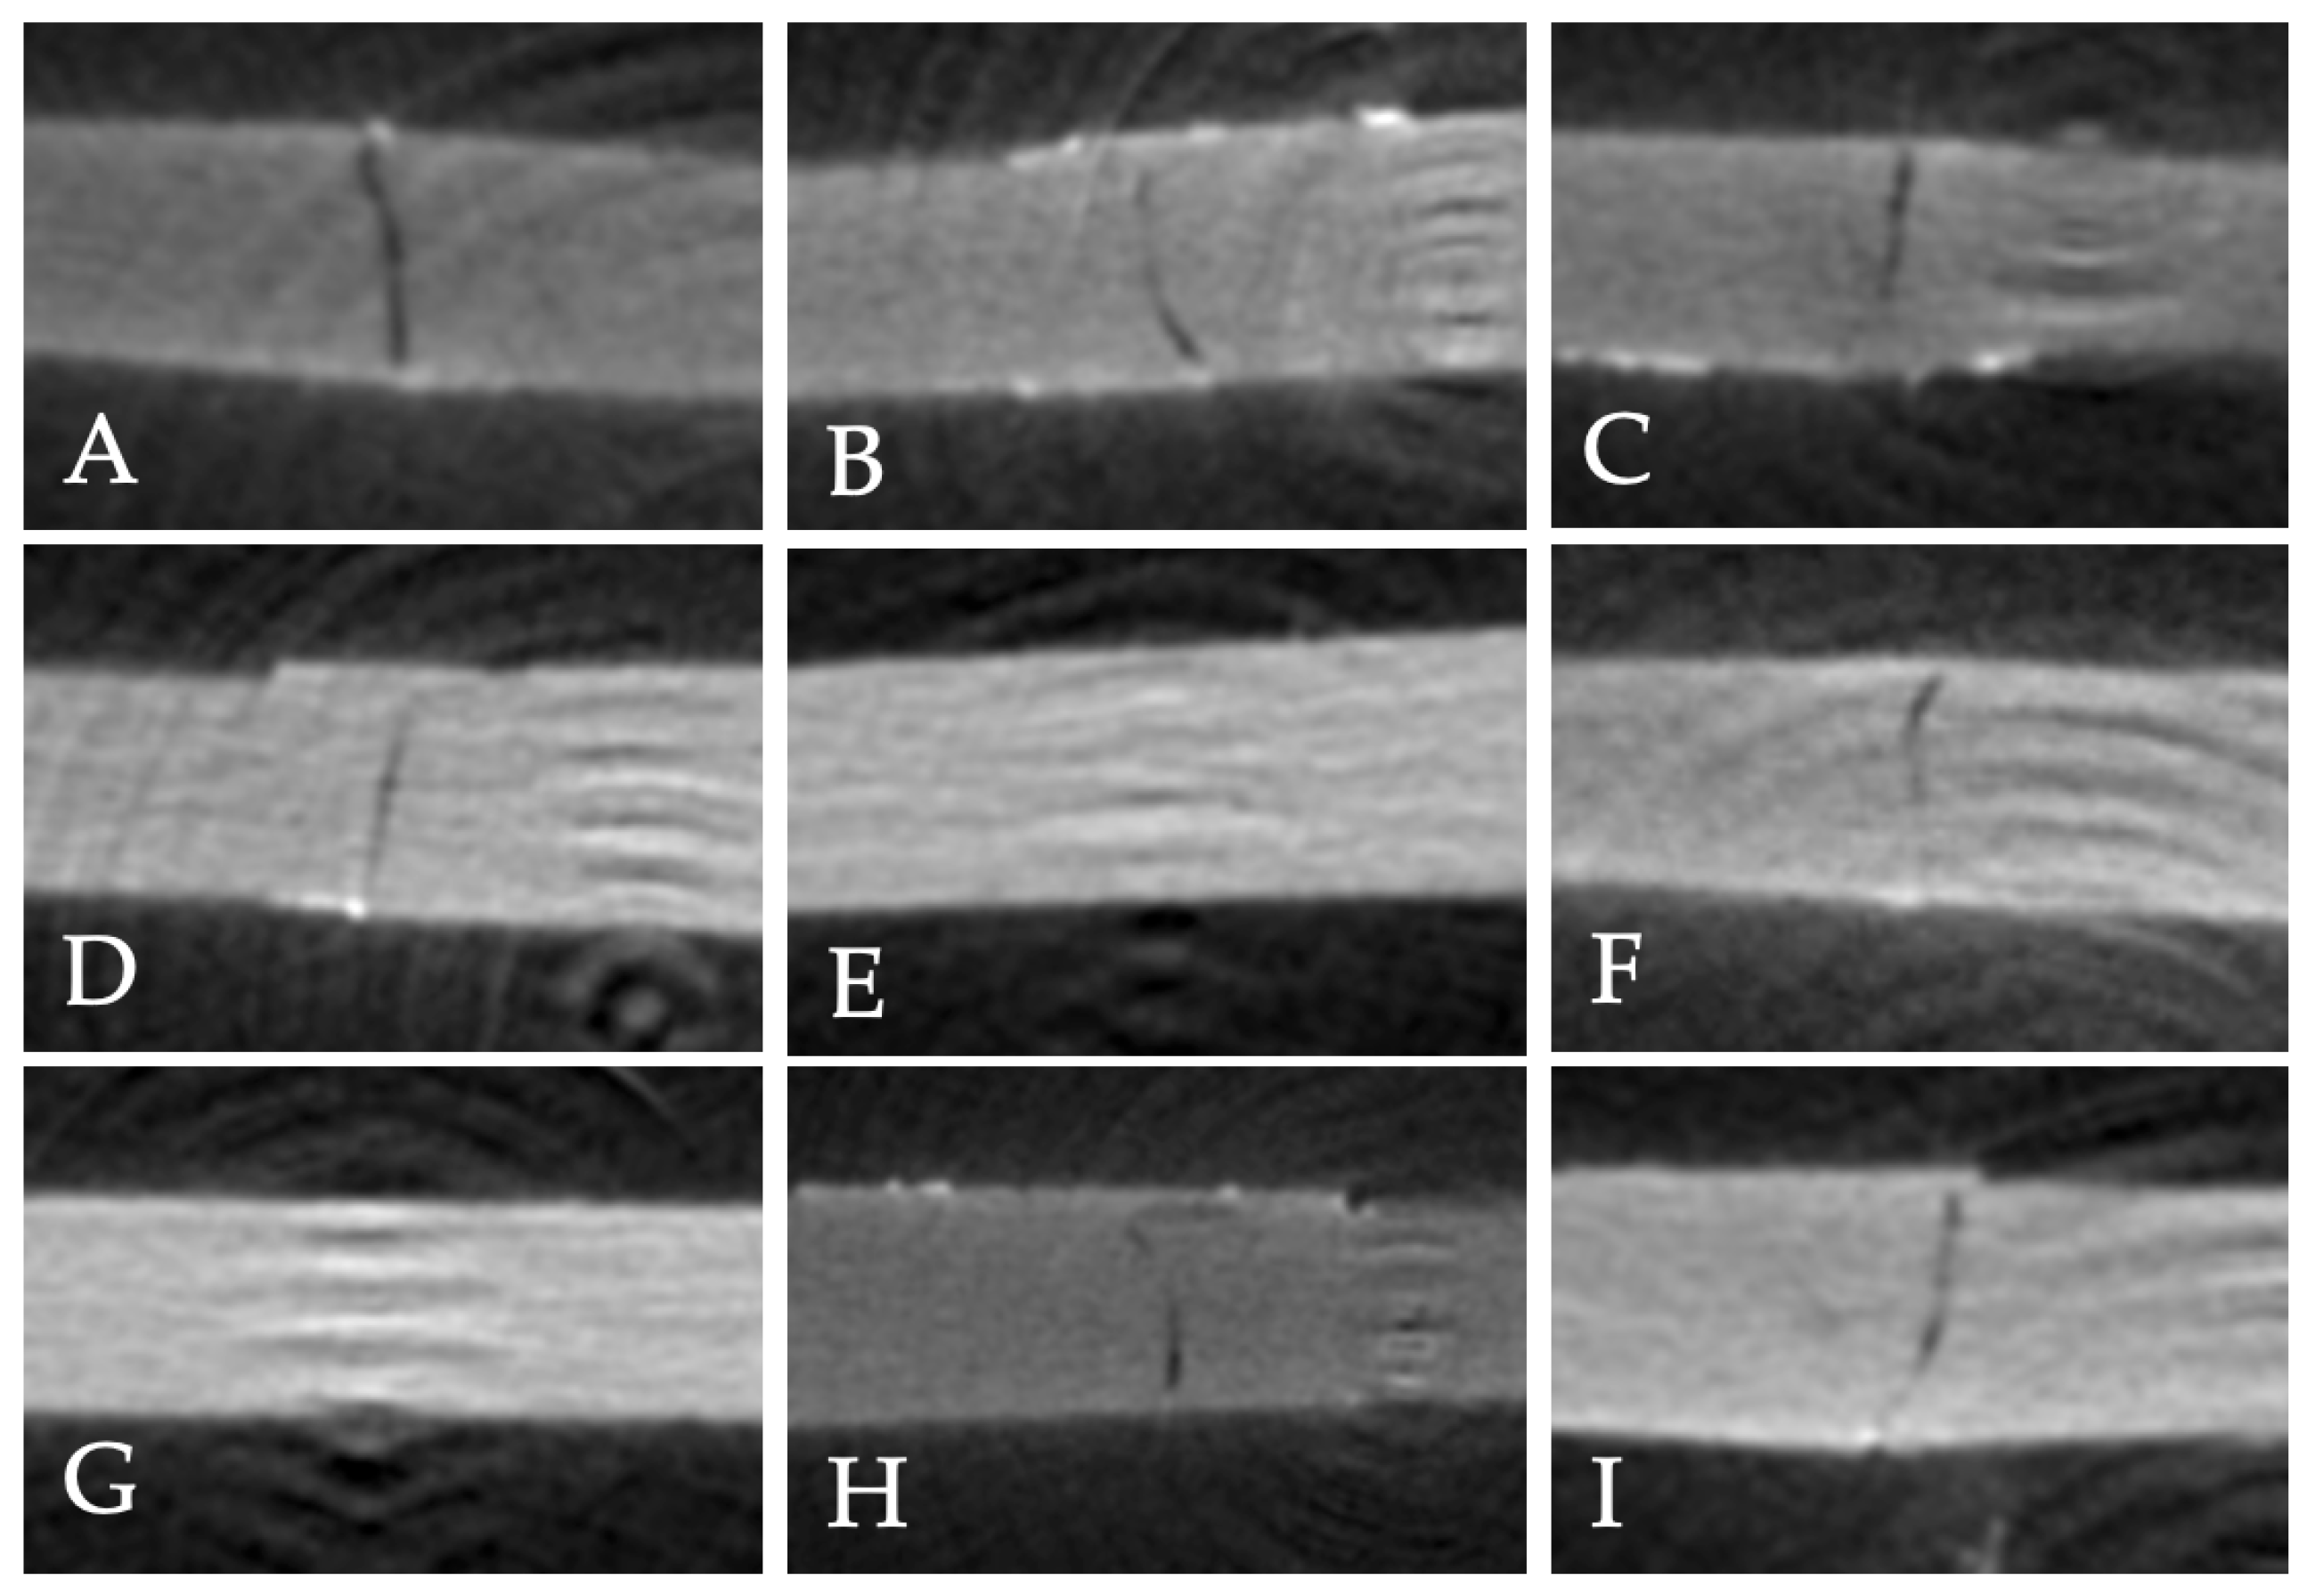

- 0 = No dye penetration

- 1 = Dye penetration up to one-half of the repair interface

- 2 = Dye penetration beyond one-half of the interface, without complete involvement

- 3 = Complete involvement of the repair interface

| No treatment | 0.065 (0.07) | 0.064 (0.01) a | 0.048 (0.05) | 0.404 |

| Diamond bur | 0.015 (0.01) | 0.011 (0.02) b | 0.016 (0.02) | 0.626 |

| Air abrasion | 0.015 (0.02) | 0.016 (0.02) b | 0.021 (0.01) | 0.808 |

| p | 0.269 | <0.001 * | 0.389 | |

| Repair Protocol | Bonding Materials | Scores | |||

|---|---|---|---|---|---|

| 0 | 1 | 2 | 3 | ||

| No treatment | G-Premio Bond | 3 (37.5%) | - | 3 (37.5%) | 2 (25%) |

| Clearfil SE Bond | - | 6 (75%) | 2 (25%) | - | |

| Adper Single Bond 2 | 5 (62.5%) | 1 (12.5%) | 2 (25%) | - | |

| Diamond bur | G-Premio Bond | 3 (37.5%) | 5 (62.5%) | - | - |

| Clearfil SE Bond | 5 (62.5%) | 3 (37.5%) | - | - | |

| Adper Single Bond 2 | 5 (62.5%) | 3 (37.5%) | - | ||

| Air abrasion | G-Premio Bond | 5 (62.5%) | 3 (37.5%) | - | - |

| Clearfil SE Bond | 6 (75%) | 2 (25%) | - | - | |

| Adper Single Bond 2 | 3 (37.5%) | 5 (62.5%) | - | - | |